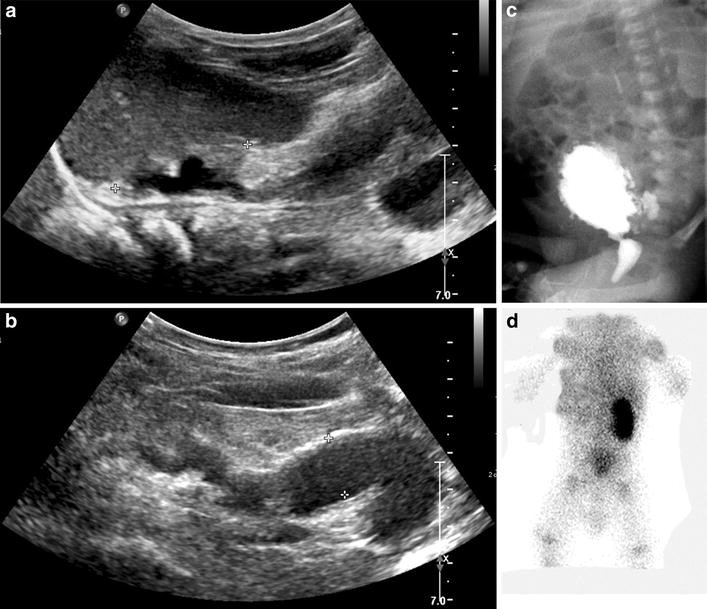

Successful in utero endoscopic ablation of posterior urethral valves a Endoscopic Valve Ablation the urodynamic exams were performed about 6 months after operation. in newborns with posterior urethral valves (puvs), the first step in treatment is to relieve bladder outlet. If the diagnosis of puv is suspected, bladder drainage is recommended, preferably with. endoscopic valve ablation, the gold standard in the definitive management of puv was done in our patients. Endoscopic Valve Ablation.